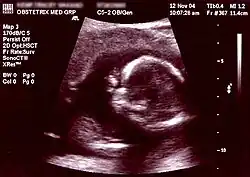

Obstetric ultrasonography, or prenatal ultrasound, is the use of medical ultrasonography in pregnancy, in which sound waves are used to create real-time visual images of the developing embryo or fetus in the uterus (womb). The procedure is a standard part of prenatal care in many countries, as it can provide a variety of information about the health of the mother, the timing and progress of the pregnancy, and the health and development of the embryo or fetus.

The International Society of Ultrasound in Obstetrics and Gynecology (ISUOG) recommends that pregnant women have routine obstetric ultrasounds between 18 weeks' and 22 weeks' gestational age (the anatomy scan) in order to confirm pregnancy dating, to measure the fetus so that growth abnormalities can be recognized quickly later in pregnancy, and to assess for congenital malformations and multiple pregnancies (twins, etc).[1] Additionally, the ISUOG recommends that pregnant patients who desire genetic testing have obstetric ultrasounds between 11 weeks' and 13 weeks 6 days' gestational age in countries with resources to perform them (the nuchal scan). Performing an ultrasound at this early stage of pregnancy can more accurately confirm the timing of the pregnancy, and can also assess for multiple fetuses and major congenital abnormalities at an earlier stage.[2] Research shows that routine obstetric ultrasound before 24 weeks' gestational age can significantly reduce the risk of failing to recognize multiple gestations and can improve pregnancy dating to reduce the risk of labor induction for post-dates pregnancy. There is no difference, however, in perinatal death or poor outcomes for infants.[3]